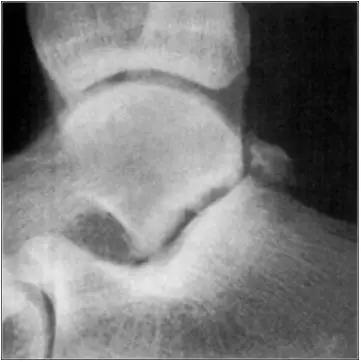

- 踝关节正侧位X 线平片,侧位片均显示距骨后方有三角形或椭圆形的距后三角骨。部分病例伴有轻度的踝关节骨性关节病。

- MRI 检查示距后三角骨及周围软组织有水肿信号,距后三角骨和距骨之间正常的低信号纤维连接中断,出现液性信号。